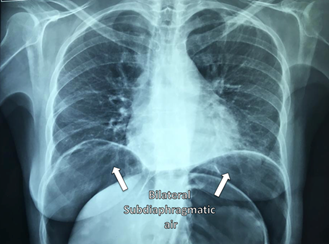

Laboratory tests showed: Hemoglobin: 13.2g/dl, Hematocrit: 41.3%, Leucocytes: 7.8103/L, Bands: 2%, Platelet: 353103/L, BUN: 14.2mg/dl, Creatinine: 0.83mg/dl, Na: 12meq, K: 3.80meq, Cl: 108meq, Ca: 6.60meq, P: 3.29meq, Albumin: 4g/dl, AST: 23U/L, ALT: 12U/L, Alkaline phosphatase: 91U/L, LDH: 244U/L, Amylase: 265U/L, Lipase: 11U/L. Plain abdominal and chest X-rays showed acute gastric dilatation and massive pneumoperitoneum (Figures 1&2). Due to the medical and surgical history which included chronic use of NSAIDs, as well as her symptoms, physical exam and imaging studies, the suggestive diagnosis of hollow viscus perforation was made, so an exploratory laparoscopy was performed to address the problem. Laparoscopic inspection of the abdominal cavity, revealed free serous fluid in the pelvic cavity without evidence of sepsis or intestinal fluid (Figure 3). A dilated stomach without obvious perforation and gas infiltration in lesser omentum was observed (Figures 4&5). An exhaustive review was carried out throughout the small bowel from Treitz ligament to the ileocecal valve and the entire colon length to rule out possible sites of perforation, without finding any evidence of it. Aspiration of the liquid and thorough irrigation of the abdominal cavity with saline solution was performed, and finally drainage was placed in the subhepatic space. Postoperative course was uneventful. She was started on liquids at 48hs after surgery, the drainage was removed and she was discharged on the fifth day after the surgical procedure. She was seen at the office several times after this event. Currently she lives a normal life, without restrictions secondary to this episode.

Figure 2 Bilateral free subdiaphragmatic air.